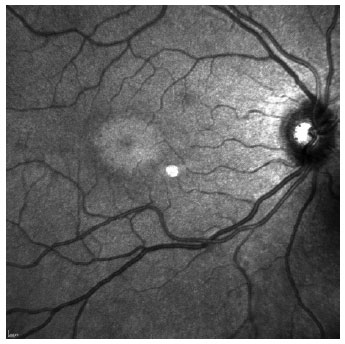

At the moderate maculopathy stage, loss of the physiological depression of the fovea occurs with interruptions of the RPE and ISOS in the parafoveal and perifoveal macular regions, characterizing the aspect in comet and macula in target. In the moderate and advanced stages, a typical fundoscopic TR lesion in the form of a bull’s eye can be identified, resulting from antimalarials. The advanced stage of maculopathy occurs with increased atrophy, foveal disruption, and visual acuity loss(15).

The results were normal for 66.7% (6) of the patients with TR in the visual acuity test, for 88.9% (8) in the color vision test, and for 66.7% (6) in fundoscopy (Table 2). Most patients with TR (55.6%) had an ophthalmologic exam annually but did not undergo additional exams. One patient who had been using the drug for 5 years had the test performed just before starting treatment, and one third of patients had periodic clinical exams but not SD-OCT. Therefore, they were not diagnosed with maculopathy and continued to use antimalarials.

SD-OCT was useful for the classification of TR. Of the nine patients with TR caused by antimalarials, 44% (4) presented premacular maculopathy (Figure 1), 22% (2) at the initial stage (Figure 2), 22% (2) at the moderate stage (Figure 3), 11% (1) at the advanced stage (Figure 4), and none at the terminal stage (Table 3).

Only one patient with severe maculopathy presented alterations in the color vision test. The other six did not complain during the anamnesis and had normal ophthalmologic examinations and retinography (infrared). The only altered examination was the optical cut of the SD-OCT, which showed four patients with premacular maculopathy and two with initial maculopathy.